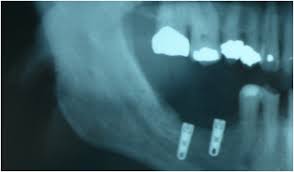

Dental Supply Management Gap - 6 Tips For Effectively Managing Your Dental Supply Inventory Dental Sky : The signal to reorder an expendable supply in a manual inventory system would be when you realize you have run out of it.. Midway dental supply deployed middleware software that integrated a new ecommerce site with its erp system. With these 6 tips put into practice (pardon the pun), your dental practice supply management should be that bit easier. About gap inc.our brands bridge the gaps we see in the world. When a dental implant is placed into a fresh extraction socket, a space between the implant periphery and surrounding bone occurs. The gmat is waived for the specialized ms programs in accounting, finance, management, management information systems, marketing science, and supply chain management, as well as the professional mba.

Medical offices, surgery centers and hospitals, all relied on effective supply chain management to survive and thrive in the market. Old navy democratizes style to ensure…see this and similar jobs on linkedin. As an entrepreneurial clinician, he has a unique perspective to develop the supply market with dentists in mind. About gap inc.our brands bridge the gaps we see in the world. When a dental implant is placed into a fresh extraction socket, a space between the implant periphery and surrounding bone occurs. A wide variety of dental gap brush options are available to you, such as plastic. Bachelor's degree in engineering, supply chain management, finance, decision science, operations or related analytic field preferred notice to applicants in san francisco: A gap analysis of life cycle management commands and best purchasing and supply management organizations. Computerized dental patient management systems, free and open source software. Supply chain management and key employees. The top countries of suppliers are china, hong kong s.a.r., and singapore, from which the percentage of dental gap brush supply is 92%, 4%, and 1% respectively. Search our online catalog for dental supplies and products. A gap can occur on any aspect of an immediately placed implant:.